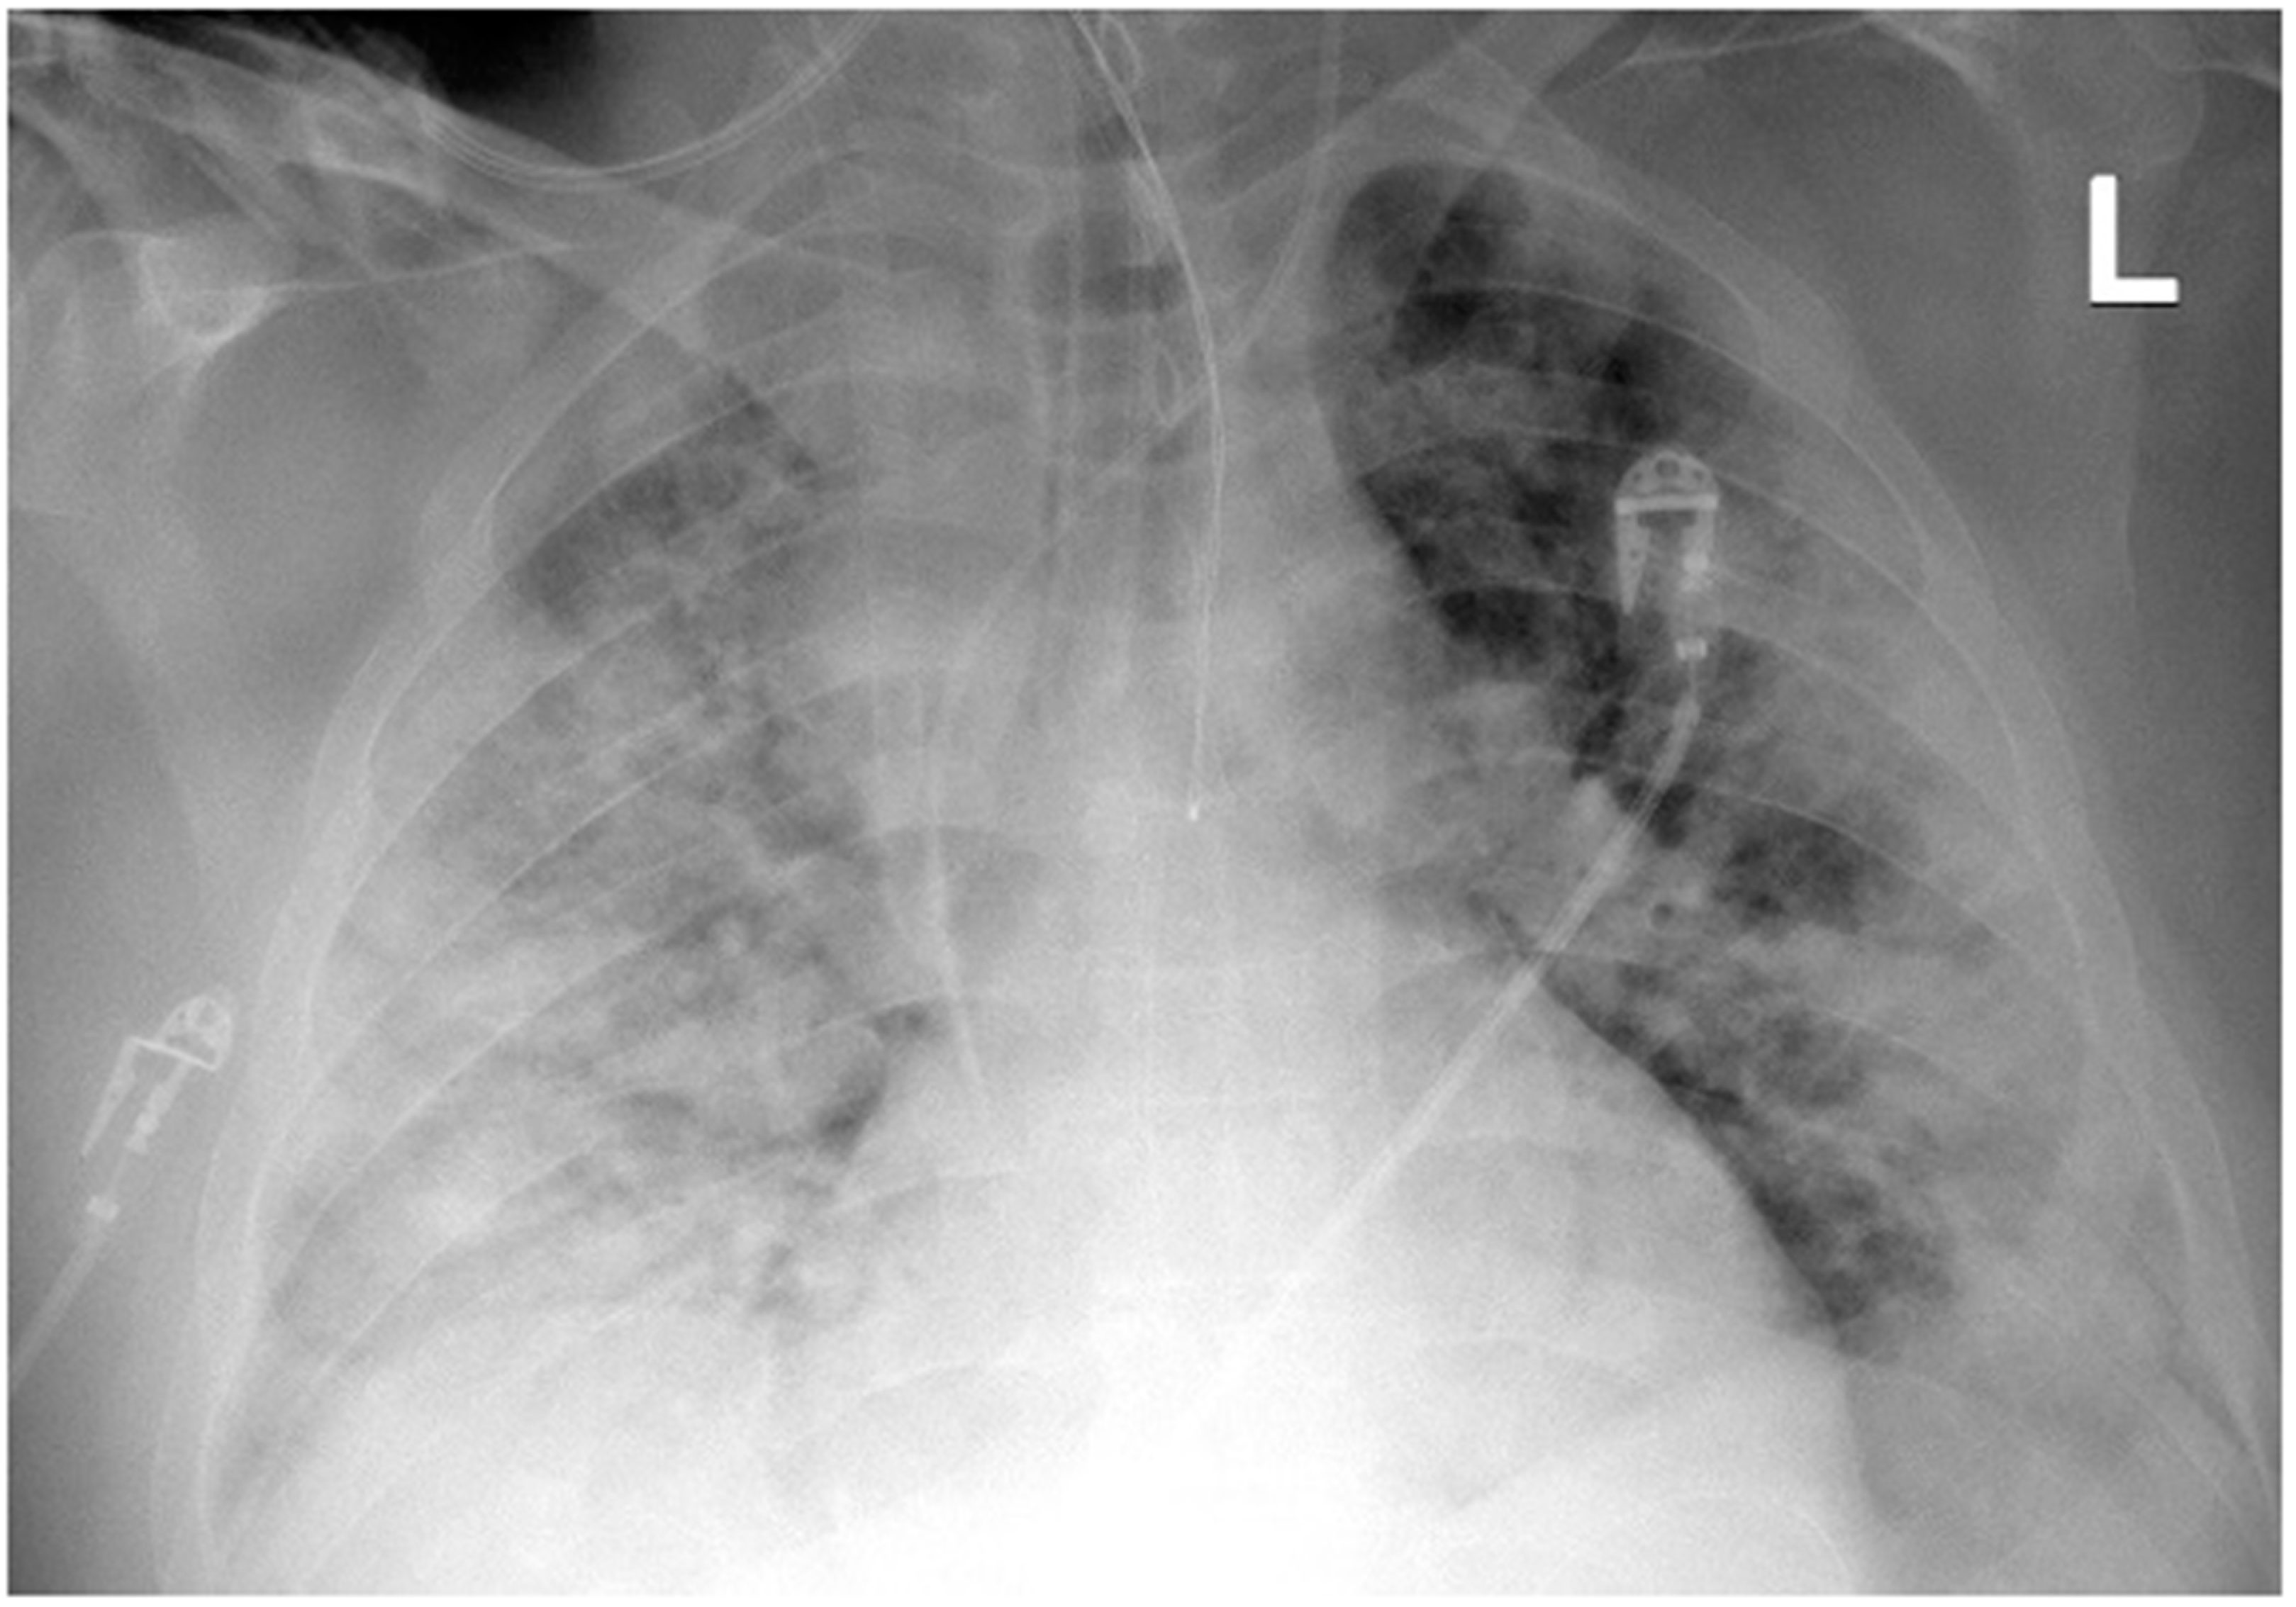

A 41-year-old obese man with BMI = 31.5 kg/m2 (class I obesity), without comorbidities, was admitted to the ICU due to symptoms of respiratory failure worsening as a result of SARS-CoV-2 infection. On admission to the ICU, a chest CT angiography scan was performed, showing signs of pulmonary embolism and ground-glass opacity inflammatory lesions, affecting up to 80% of the lung parenchyma (Figure 1).

Figure 1. Chest CT scan on admission to the ICU: (A) upper lung segments; (B) middle lung segments; (C) basal lung segments (Case 1).